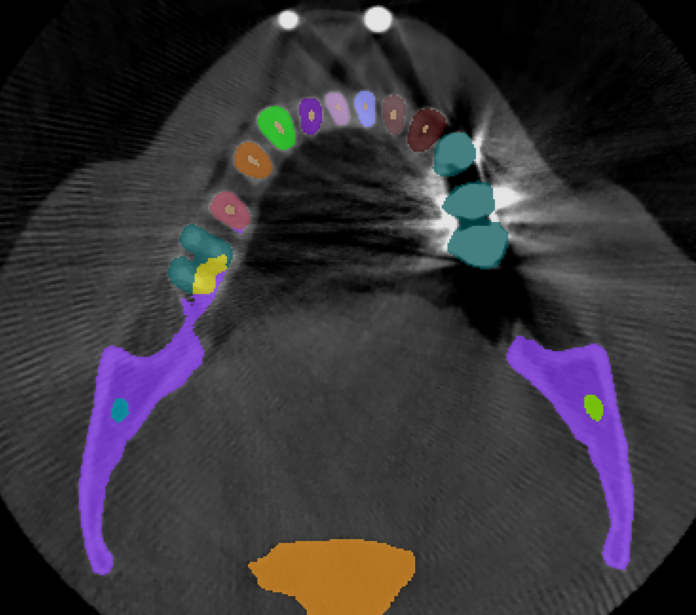

3.2 Qualitative Results

Fig.˜2 visualizes the qualitative comparison between the ground truth and our model’s predictions of the scans with the highest and lowest Dice score in the validation set, in the top and bottom rows, respectively. We observe that in most cases, U-Mamba2 produces precise segmentation predictions, showcasing the effectiveness of incorporating dental domain knowledge into the model design. Furthermore, we observe that U-Mamba2 can accurately localize the three tiny structures (ILN), producing visually acceptable segmentations. In the worst-case scenario, although the scan is imperfect due to image artifacts caused by metallic objects, false positives are primarily confined around the image edge or confusion between the actual tooth and the crown or implant, underscoring U-Mamba2’s robustness under noisy conditions.